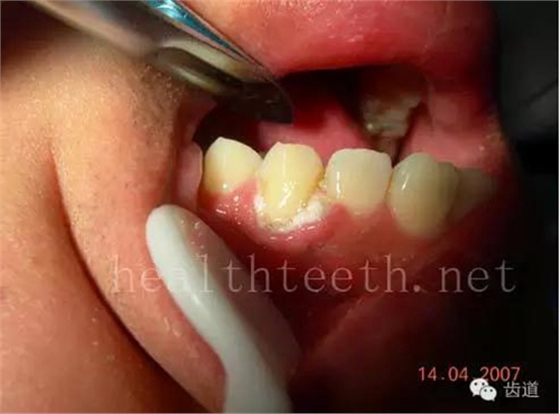

牙周大量牙石堆積

下牙的增生性齦炎,刷牙出血嚴(yán)重